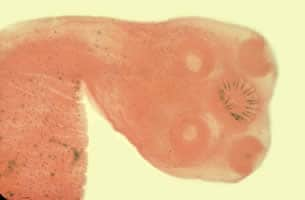

Taenia spp. scoleces.

Microscopic identification of eggs and proglottids in feces is diagnostic for taeniasis, but is not possible during the first 3 months following infection, prior to development of adult tapeworms. Repeated examination and concentration techniques will increase the likelihood of detecting light infections. Nevertheless, identification of Taenia is not possible if solely based on microscopic examination of eggs, because all Taenia species produce eggs that are morphologically identical. Eggs of Taenia spp. are also indistinguishable from those produced by cestodes of the genus Echinococcus (tapeworms of dogs and other canid hosts). Microscopic identification of gravid proglottids (or, more rarely, examination of the scolex) allows species determination.